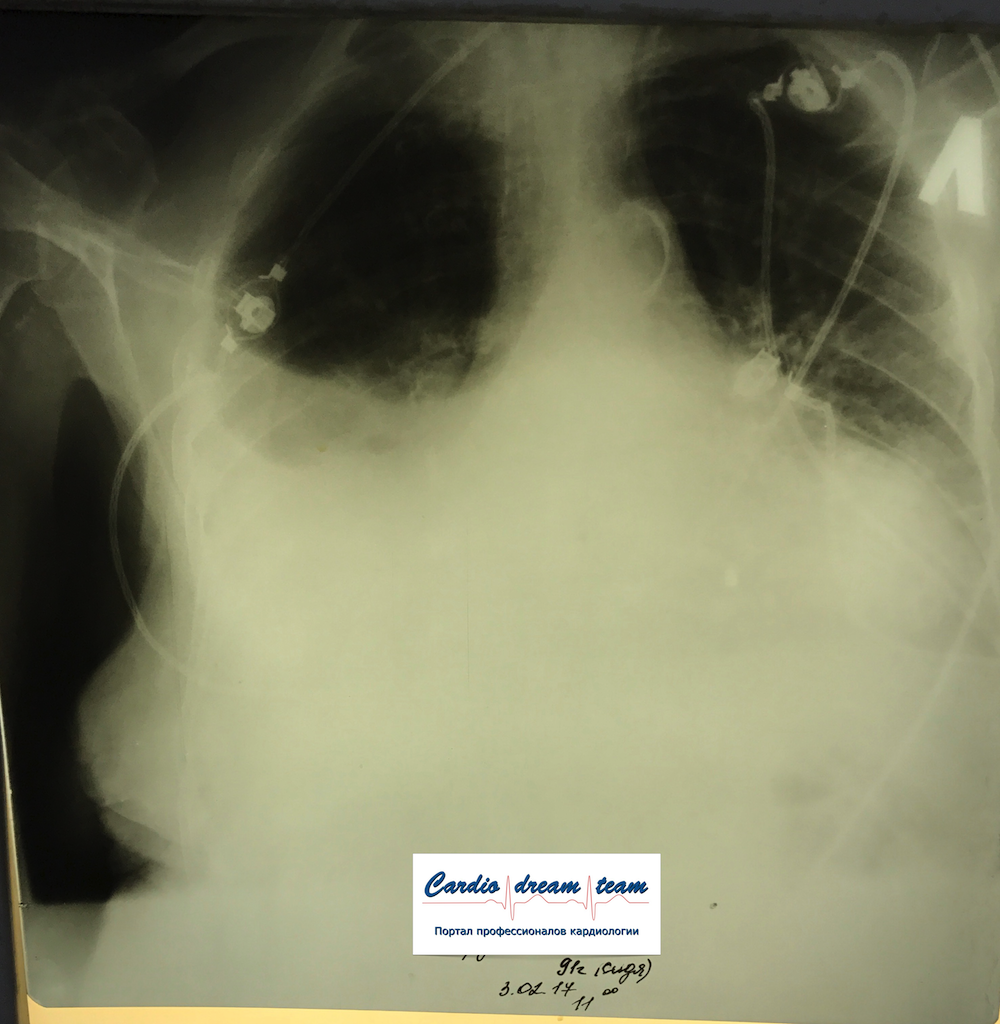

Гидроторакс. Серия снимков.

1 - лежа. Так делать не надо! Надо только сидя!

2 - сидя. Понятно, что гидроторакс за раз не победить

3 - удалено 1100.

4 - удалено ещё 1200. И диуретики все эти дни.